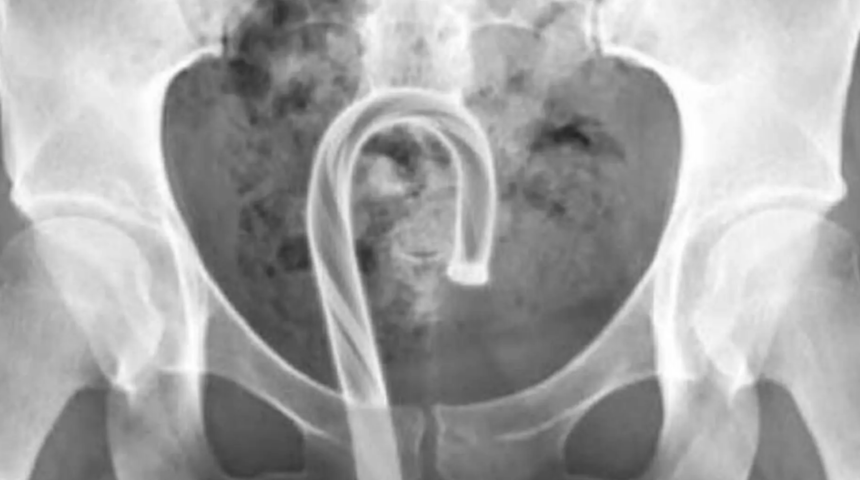

Bu sözde seks oyuncakları ile kendinizi tatmin etmekten kaçınmak, basit görünebilir; ancak, bu talihsiz trend sanıldığından daha yaygın, 2013'te yapılan bir vaka çalışmasında insanların kendilerine cam süsler yerleştirdiklerinden bahsediliyor. Bu arada, bir sağlık görevlisi Facebook grubundaki bir sosyal medya gönderisi, bir şeker kamışı ve bir ağaç dekorasyonuyla doğaçlama yapan örneklerini ve her birinin grafik X-ışınlarını gösteren fotoğrafları anlattı. "Bu röntgenler, rektuma sıkışmış bir şeker kamışı ve bir Noel ağacı top süsü gösteriyor" dedi.